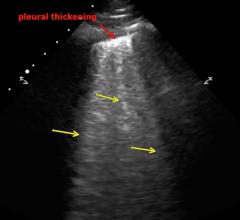

November 1, 2021 — According to ARRS’ American Journal of Roentgenology (AJR), radiologists need to be cognizant of the ...